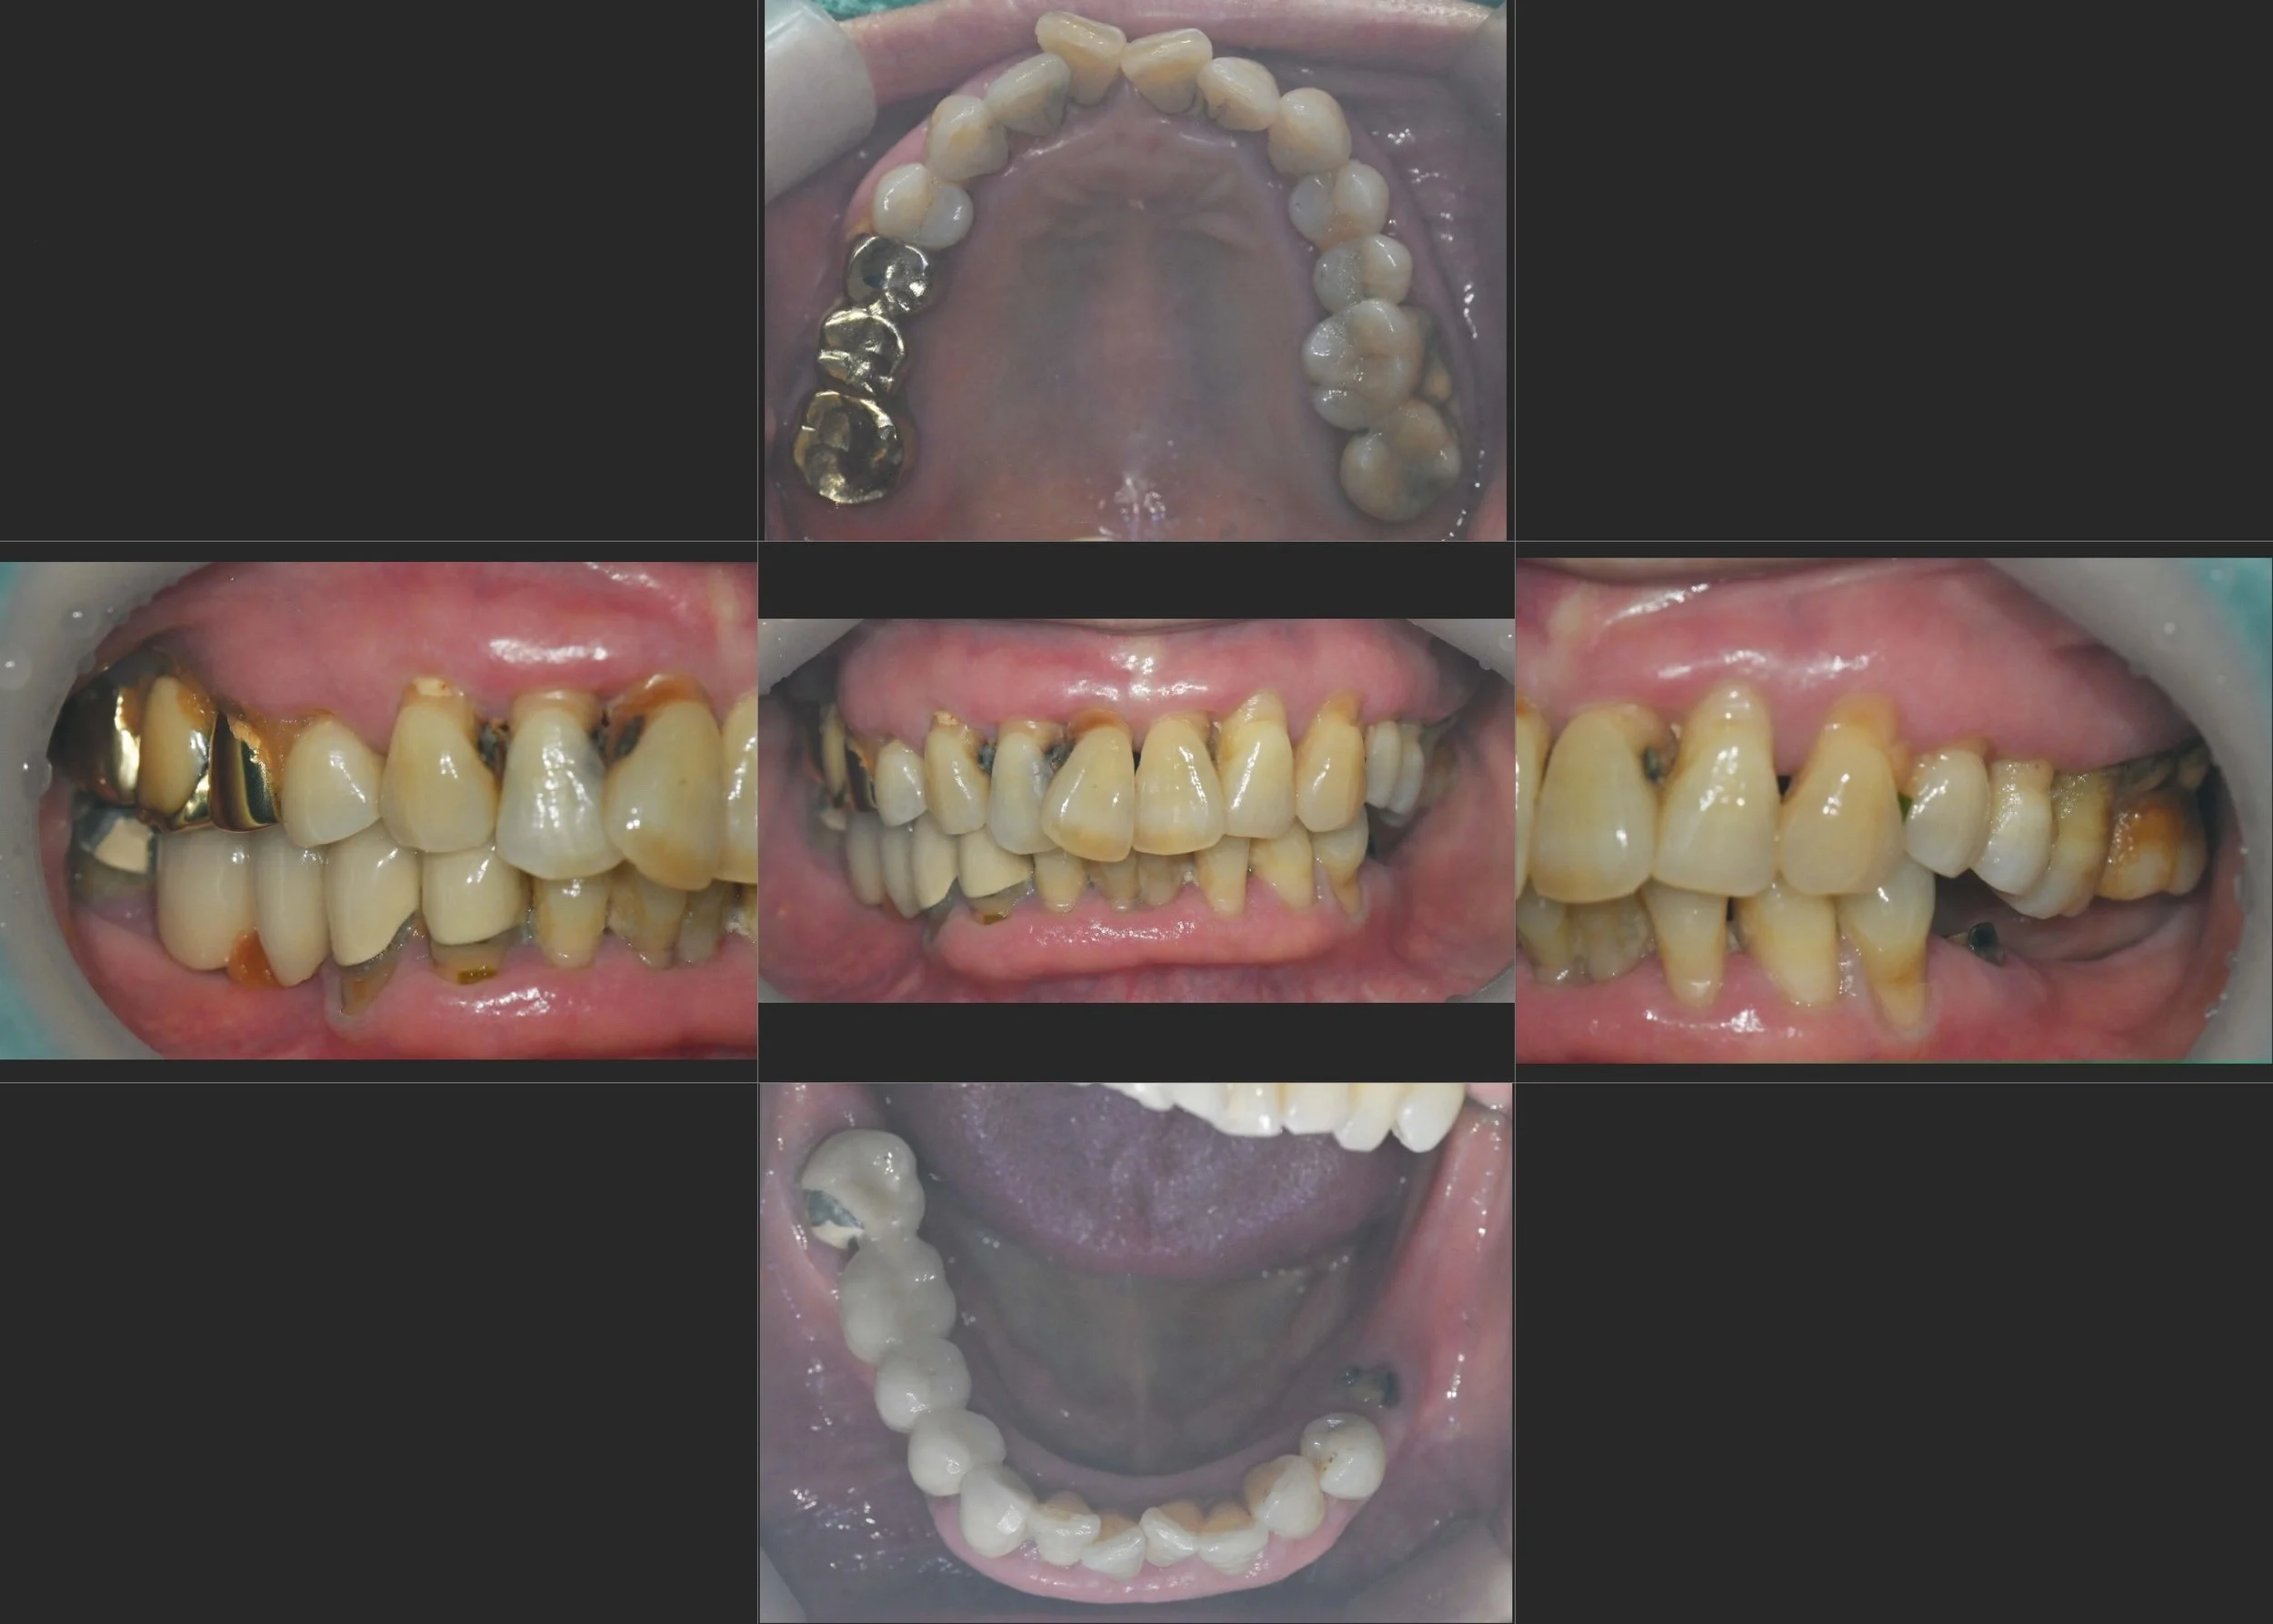

INTRA ORAL - AFTER